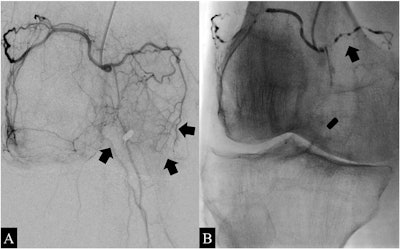

Angiograms of the right knee in a 76-year-old man with knee osteoarthritis. A) Before embolization, selective angiography of the common trunk of the superior lateral and superior medial genicular arteries shows hypervascular inflammatory blush (arrows). B) During embolization using ethiodized oil of the common trunk, the angiogram shows emulsion droplets (arrows). Image courtesy of Diagnostic and Interventional Imaging.